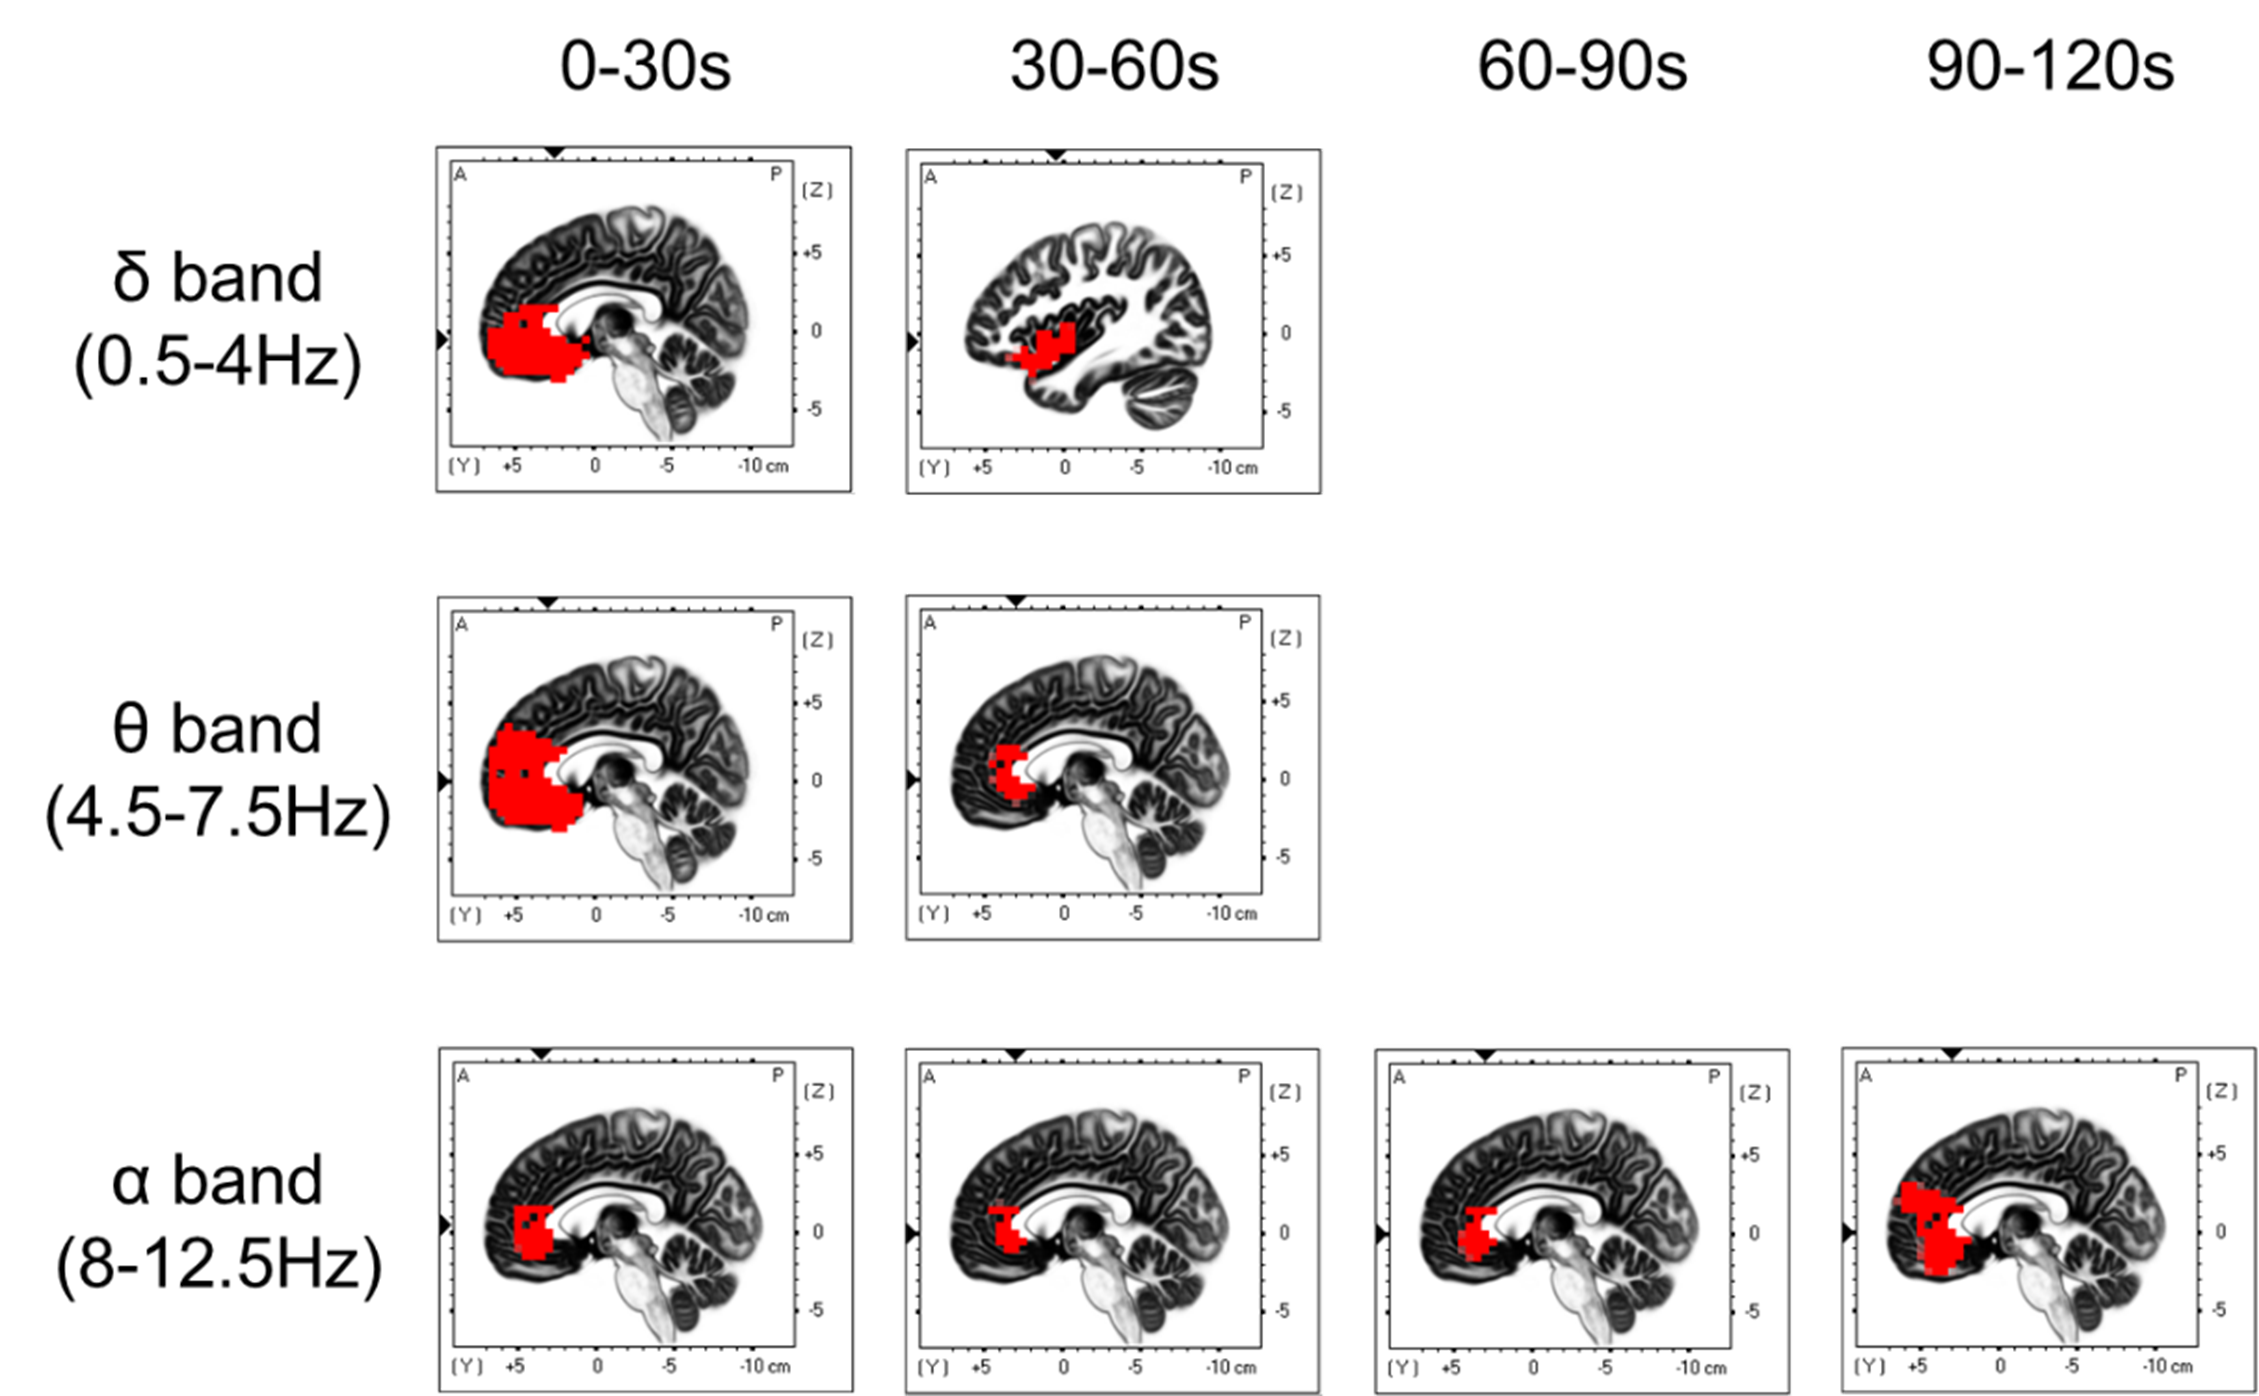

◆レモンの精油吸引直後から、デルタ帯域やシータ帯域において、帯状回(感情処理に関与する脳領域)を含む前頭前野、海馬傍回(海馬に近い領域。記憶処理に関与する脳領域)の活性化が認められました(図2)。またこれらの活性化は吸引開始後60秒まで持続しています。

図2 安静時状態と比較して、レモン精油吸入の活性化が著しく高い脳領域